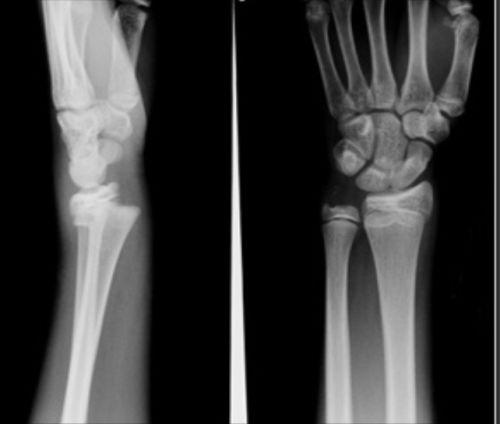

桡骨小头骨骺分离多因跌倒时肩关节外展,肘关节伸直并外翻,桡骨小头撞击肱骨小头引起,常见于儿童肘部关节损伤。桡骨小头骨骺分离能治好吗? 接下来跟大家分享下我的看法。

桡骨小头骨骺分离能治好吗?

多数病例效果良好,伸肘旋前、内翻肘关节,按压桡骨小头可复位,复位后屈时90°石膏外固定3周。撬拨复位适用于手法复位无效的歪戴帽压缩骨折且分离者。

开放复位适用于上述方法复位不满意者。一般复位后不需钢针固定,仅陈旧性骨折复位后用克氏针内固定,以免术后移位。

骨骺融合前的桡骨小头骨骺分离不宜切除桡骨小头,否则可明显影响前臂发育。饮食清淡有营养,注意膳食平衡宜钙质丰富的食品,如牛奶、奶酪、酸奶、豆制品;多吃新鲜绿色蔬菜。

相关图片